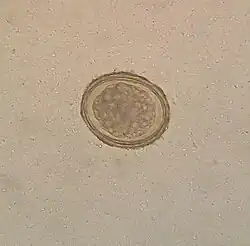

Ascaris lumbricoides is characterized by its great size. Males are 2–4 mm (0.08–0.2 in) in diameter and 15–31 cm (5.9–12 in) long. The male's posterior end is curved ventrally and has a bluntly pointed tail. Females are 3–6 mm (0.1–0.2 in) wide and 20–49 cm (7.9–19 in) long. The vulva is located in the anterior end and accounts for about one-third of its body length. Uteri may contain up to 27 million eggs at a time, with 200,000 being laid per day. Fertilized eggs are oval to round in shape and are 45–75 μm (0.0018–0.0030 in) long and 35–50 μm (0.0014–0.0020 in) wide with a thick outer shell. Unfertilized eggs measure 88–94 μm (0.0035–0.0037 in) long and 44 μm (0.0017 in) wide.[9]